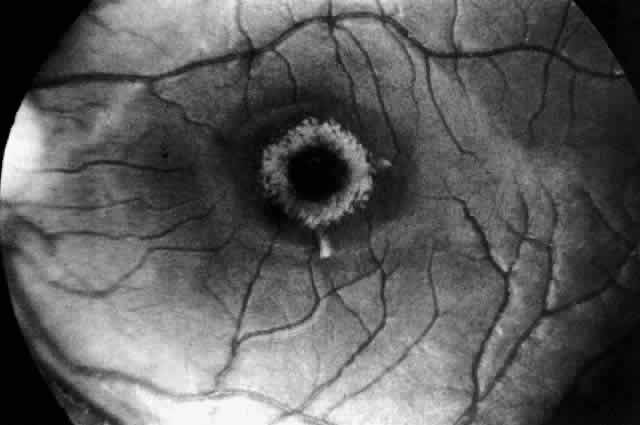

In three patients with type III subacute juvenile neuronopathic Gaucher's disease however, the retina showed a unique retinopathy. The findings in Cogan's case 1 are described: “Both fundi showed discrete white spots randomly distributed in the posterior fundus, especially along the inferior vascular arcades (Fig. 8). The spots varied in diameter from just visible to approximately 0.1 mm and were situated in the superficial retina or on the surface of the retina. Several covered the retinal vessels. The disc and retinal vessels were normal.” The child, an 11-year-old boy, had normal acuity and a full field of vision by confrontation. He had presented at age 3 years with splenomegaly.

Fig. 8. Fundus of a patient with type III subacute juvenile neuronopathic Gaucher"s disease showing discrete white spots in or on the retina along the inferior vascular arcades. At least one spot overlies a vein. The optic disc and retinal vessels were normal. (Cogan DG, Chu FC, Gittinger J, Tyshsen L: Fundal abnormalities of Gaucher"s disease. Arch Ophthalmol 98:2202, 1980. Copyright © 1980, American Medical Association)

Normal vision and similar retinal abnormalities were observed in a mildly mentally retarded 18-year-old woman (case 2) presenting with splenomegaly at age 1 year and in a 6½-year-old boy (case 3) noted to have hepatosplenomegaly in the first year of life. The patients in cases 1 and 3 had conspicuous supranuclear defects of eye movement.

Japanese observers Yanagida, Matsumoto, Tokudo, and Hirose were the first to report the peculiar retinal spots in type III juvenile Gaucher's disease between 1950 and 1965. Their clinical reports in Japanese journals are referenced in Cogan and colleagues' paper.81